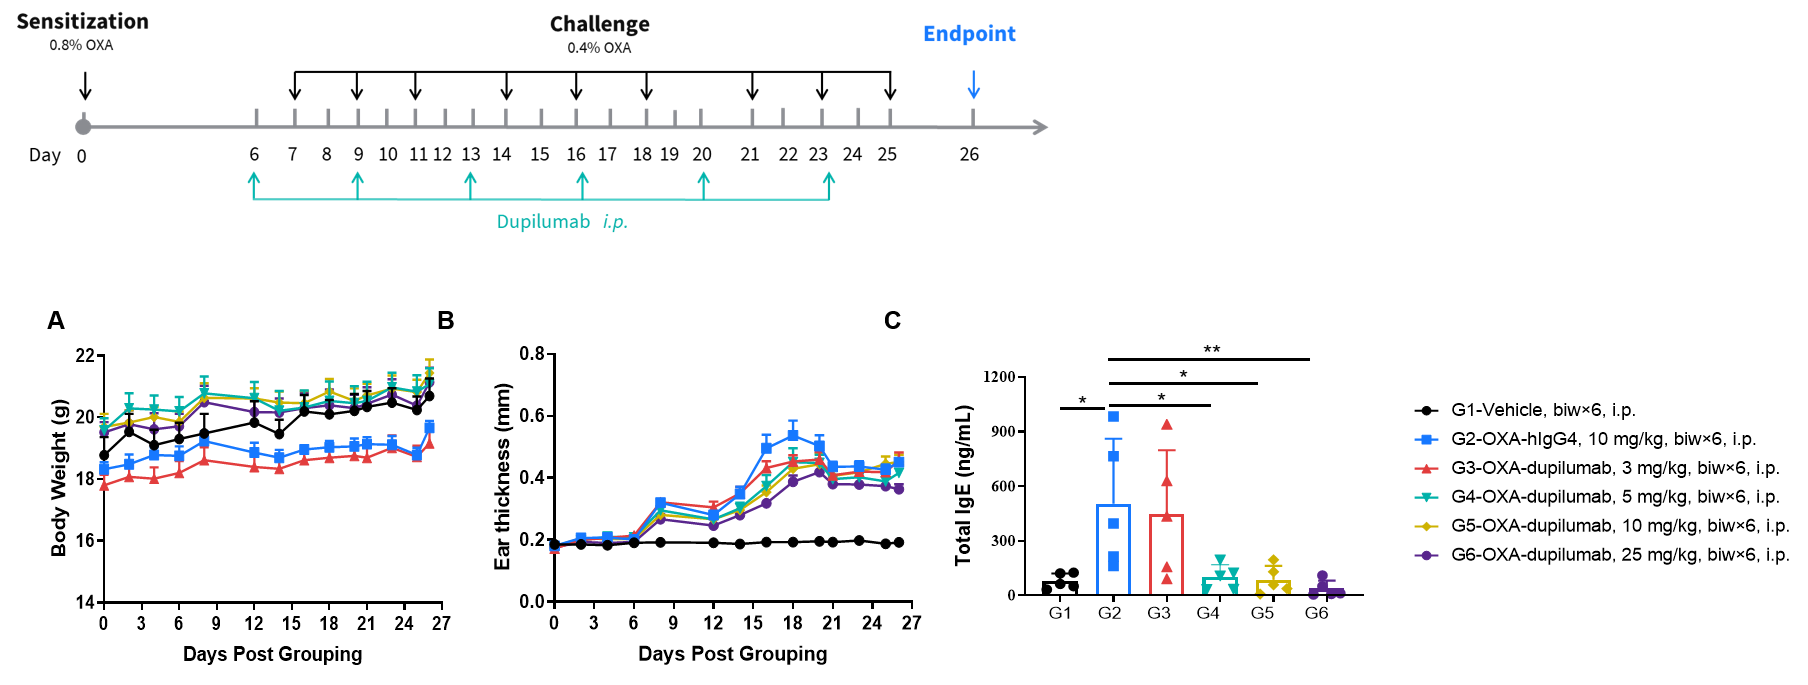

Efficacy of anti-human IL4RA antibody in B-hIL4/hIL4RA mice. Mice in each group were treated with different dose of dupilumab produced in house. Doses are shown in legend. (A) Body weight changes during treatment. (B) Statistical analysis of ear thickness in each group. Epidermis of ear began to desquamate from day 18. So the ear thickness was decreased from day 18 as shown in figure. (C) Total IgE levels in serum. Total IgE levels were measured by ELISA on day 26. Ear thickness and concentrations of total serum IgE were negative related with the doses of antibody. (n = 5).

Effects of anti-human IL4RA antibody on inflammatory infiltration in ear skin of the AD mouse model. (A) Hematoxylin and eosin (H&E) staining. (B) Score of eosinophils infiltrated in ear epidermal skin (n=5). Infiltration scores of eosinophils in ear skin were negatively related to the doses of antibody, demonstrating that the B-hIL4/hIL4RA mice provide a powerful preclinical model for in vivo evaluation of anti-human IL4RA antibodies. AD: Atopic dermatitis; ND: Not detectable.